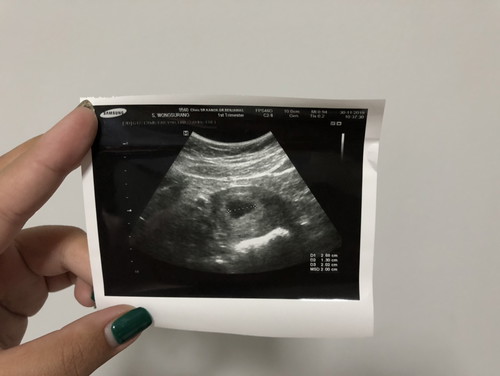

ซาวน์ตอน 6 weeks เจอถุงน้ำไม่เจอลูก

ไปซาวน์มาตอน 6 weeks เจอแต่ถุงน้ำไม่เจอลูกค่ะ อีก 2 สัปดาห์หมอนัดไป จะมีโอกาสกลายเป็นท้องลมไหมคะ กลัว ?